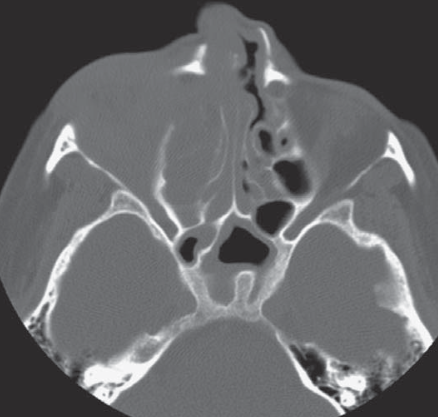

Wegener (ORL)

Général

Comblement sinusien

Erosions

Epistaxis